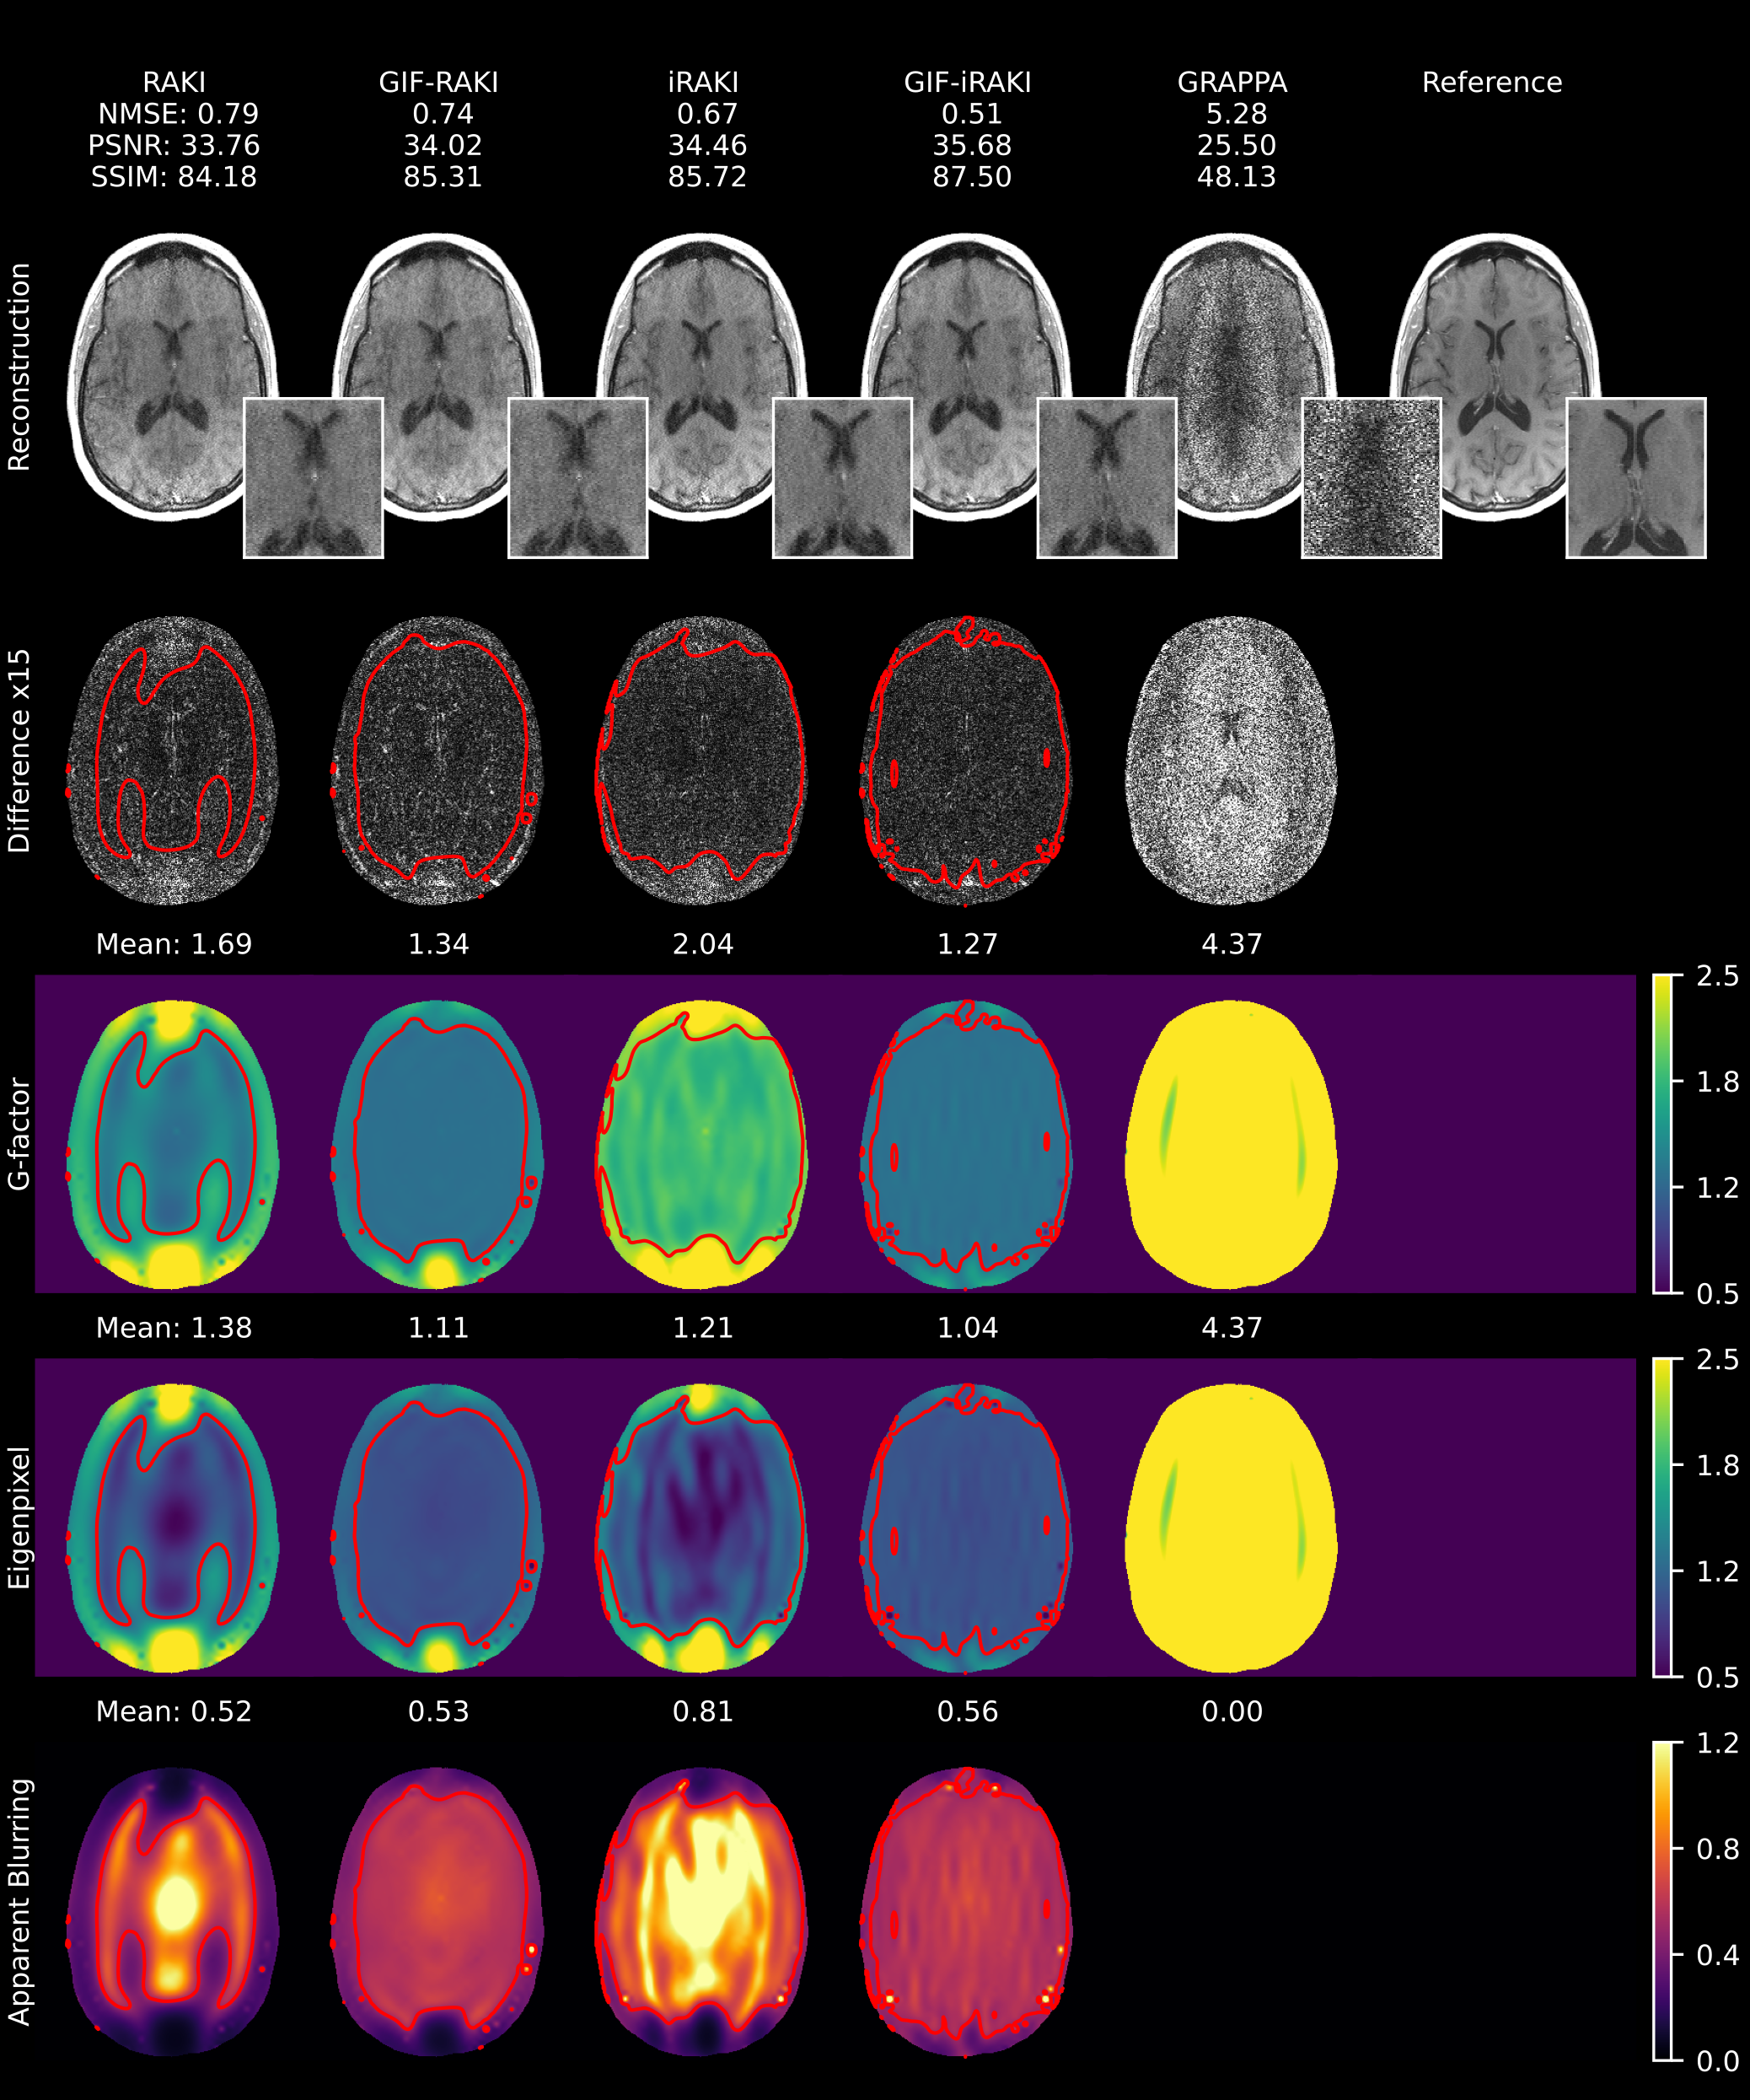

GIF-iRAKI outperforms other RAKI variants under aggressive undersampling (R=6R=6, ACS=48\text{ACS}=48), achieving a target g-factor of γgfactortarget=1.25\gamma_{\mathrm{gfactor}}^{\mathrm{target}}=1.25 as confirmed by quantitative metrics (Figure 9). Zoomed magnitude images reveal central blurring hotspots in standard RAKI and iRAKI that are effectively mitigated by the GIF-based variants. Furthermore, variance regularization prevents linear eigenpixel maps from falling below one. Training loss curves for GIF-iRAKI across eight refinement iterations are provided in Supplementary Figure 8.

Variance regularization beneficially influences image quality. Minimizing the g-factor imposes an absolute constraint on the overall noise level, while the apparent blurring regularization balances the ratio between linear and nonlinear components within the total variance (Figure 7 and 8, Supplementary Figure 1 and 2). These observations justify a regularization strategy that prioritizes achieving specific apparent blurring targets at lower g-factor levels. For the joint g-factor-apparent blurring loss gfactor+blurG\mathcal{L}_{\text{gfactor+blur}}^{\scriptscriptstyle\text{G}} specifically, targets of γgfactortarget=1.25\gamma_{\mathrm{gfactor}}^{\mathrm{target}}=1.25 and γblurtarget=0.5\gamma_{\mathrm{blur}}^{\mathrm{target}}=0.5 were proved to be effective for conservative variance regularization at the group level as well (Figure 10). The higher apparent blurring level imposed by variance regularization translated into elevated SSIM scores compared to RAKI. This indicates the metric’s inherent bias toward image smoothness, as previously documented Mason et al. [2020-04], Pambrun and Noumeir [2015]. Furthermore, gfactor+blurG\mathcal{L}_{\text{gfactor+blur}}^{\scriptscriptstyle\text{G}} encourages homogeneous variance maps and prevents the eigenpixel variance from dropping below one, thus avoiding non-physical scenarios. Simultaneously, it suppresses the network’s tendency to replace noisy regions with nonlinear signal mixing from other pixel locations, thereby reducing the central blurring hotspots (Figure 9).